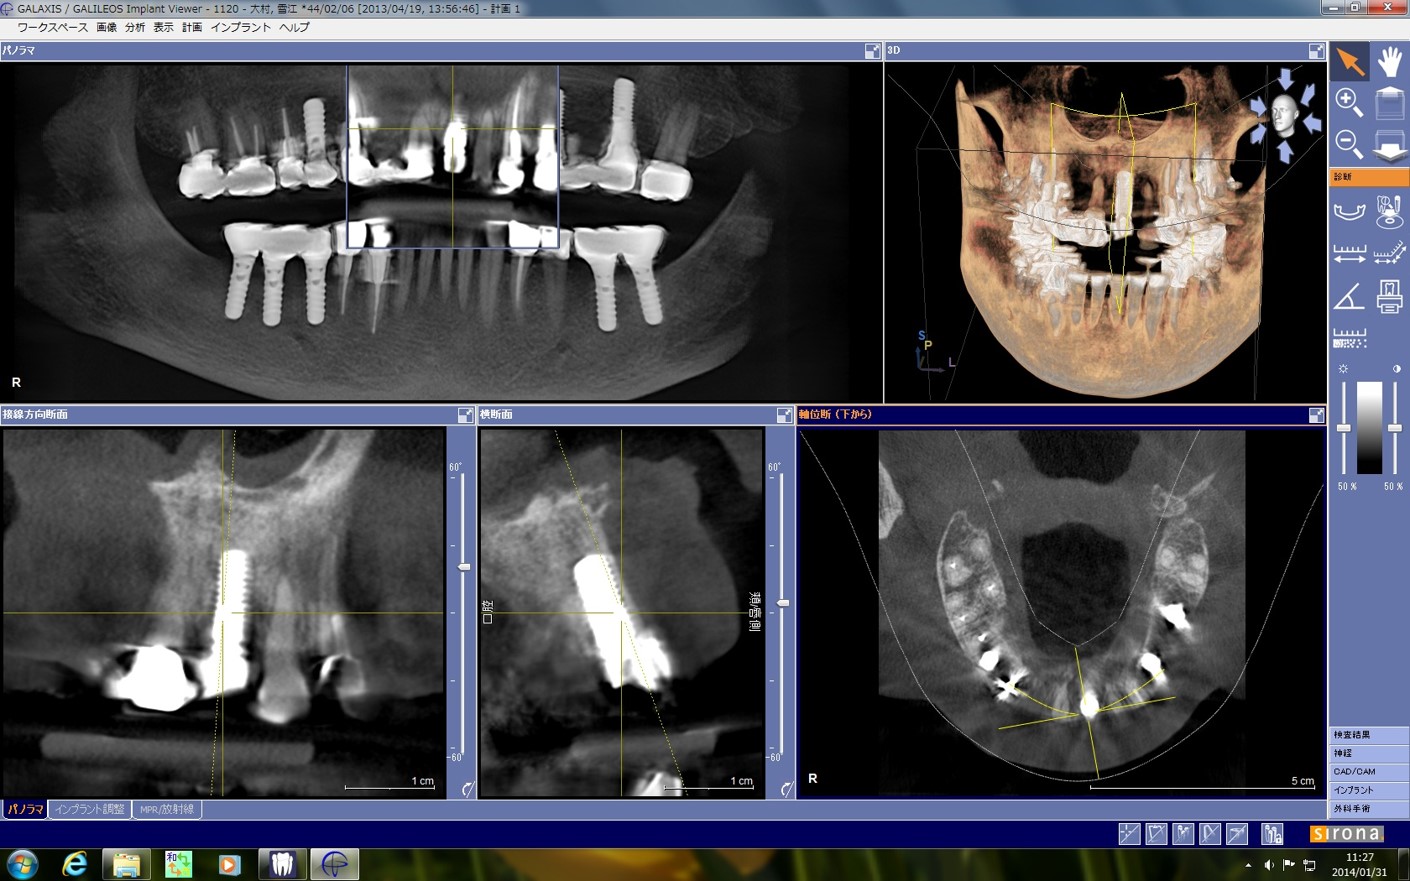

セレックのデータをプランニングソフトに取り込んで、埋め込みのポジションを設定します。この後、データをインターネットでドイツのSICAT社へ転送します。

インプラント埋入後のCTですが、所定の位置にピンポイントで入っています!